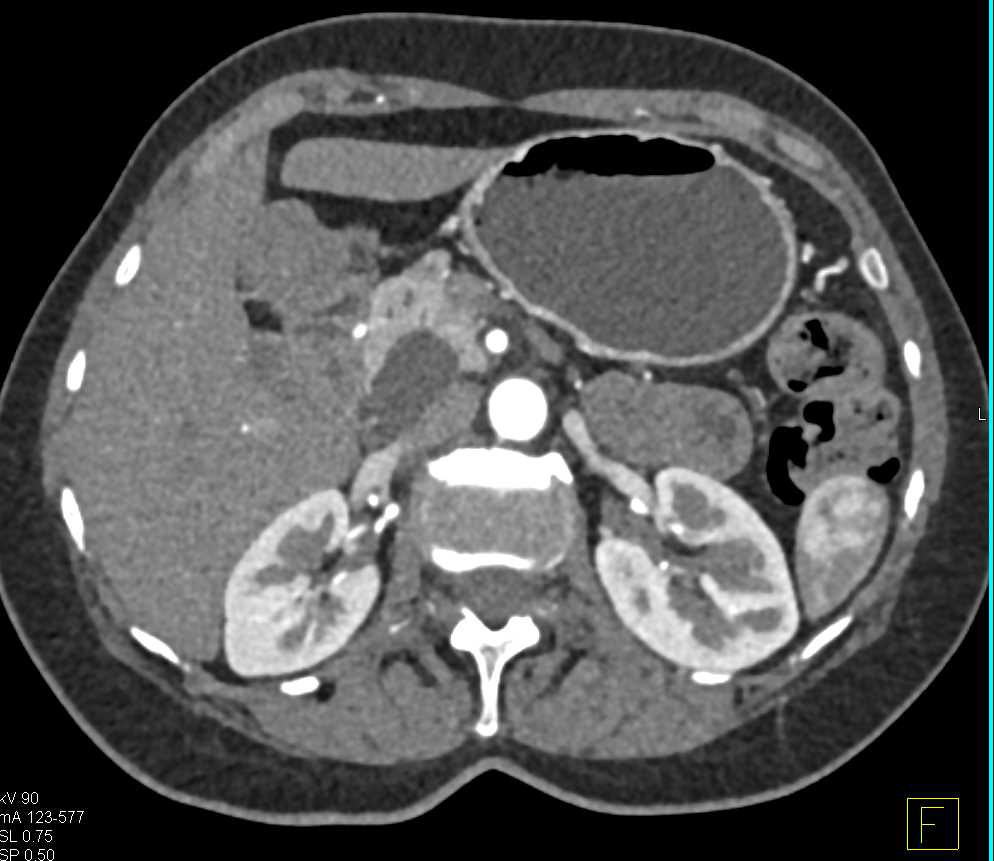

Pancreas Adenocarcinoma with Pancreatic Duct Cutoff